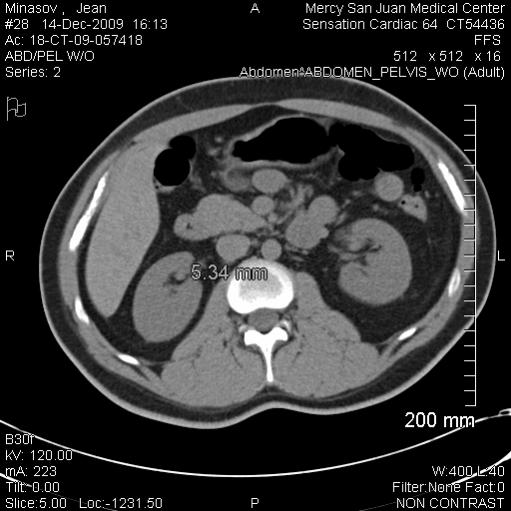

Right kidney: There is a 5 mm calculus at the ureteropelvic

junction on the right without hydronephrosis. The right ureter

is decompressed. No additional calculi in the ureter. No

recently passed stones in the bladder or upper urethra. No

perinephric fluid surrounding the right kidney. No gross mass

identified on this very limited scan.